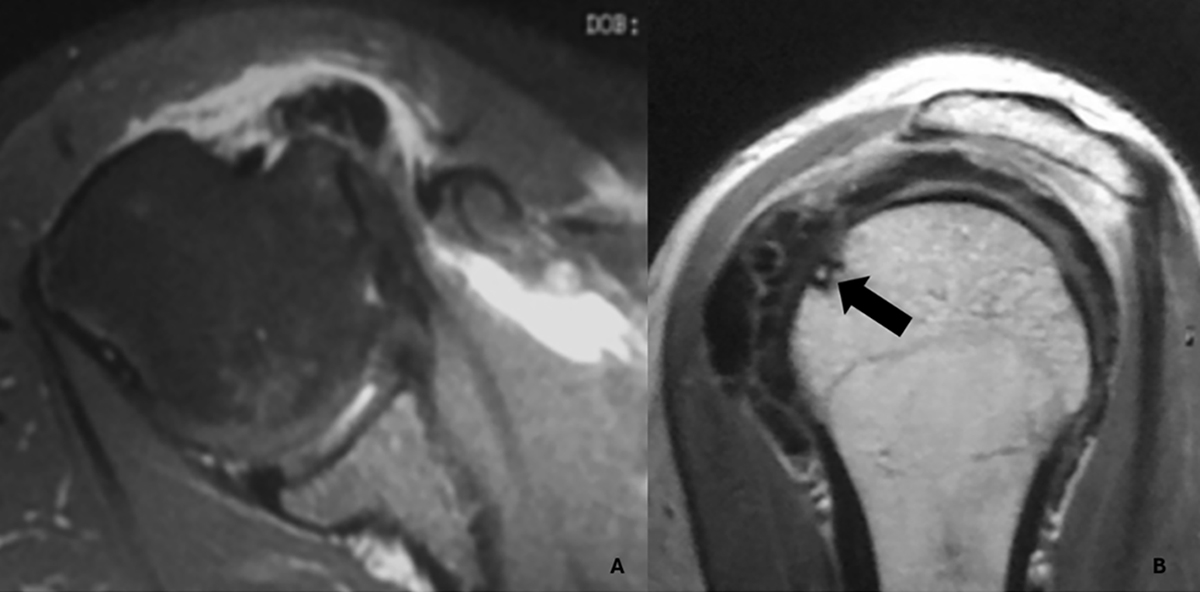

Magnetic resonance imaging of a Type III-a calcification in the subscapularis tendon. A. Axial view showing a calcific deposit in direct contact with the cortex of the lesser tuberosity, associated with marked subcoracoid bursitis. B. Oblique sagittal view demonstrating focal cortical erosion at the site of contact (black arrow), without evidence of intraosseous extension.